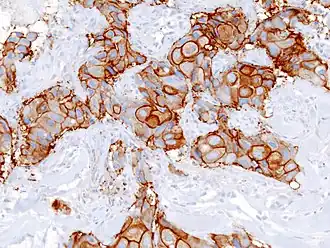

Imagen histopatológica de un carcinoma ductal infiltrante de mama. | ||

El carcinoma ductal infiltrante (CDI), también conocido como carcinoma invasivo de ningún tipo especial y anteriormente conocido como carcinoma ductal invasivo no especificado, es la forma más frecuente de cáncer de mama invasiva constituyendo un 80% de todos los casos y se caracteriza por ser una masa o tumoración con límites no bien delimitados.[1] En la mamografía aparece con bordes mal constituidos con trabéculas y tejido graso con áreas de necrosis y hemorragia que pueden aparecer como calcificaciones. En el examen físico, la tumoración tiene una constitución más rígida o firme que las lesiones benignas del seno. Bajo el microscopio, las células cancerosas invaden y reemplazan los tejidos circundantes normales.